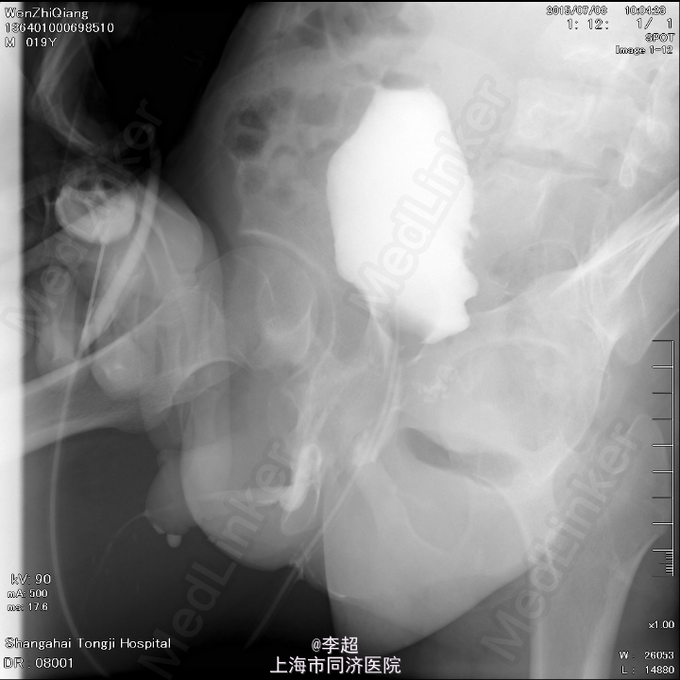

查体 辅查

患者尿道开口于阴囊下,会阴部,无法控尿,尿液自行流出 尿道造影仅显示假道,正常尿道仅存留阴茎短尿道,约5cm长

择期行耻骨下缘切除+阴囊皮瓣代尿道成形+尿道膀胱拖入术 手术过程:行会阴部倒Y形切口切口,切口包括会阴部尿道造口处,术中见阴茎部尿道存在尿道-阴茎皮肤瘘道,予切除瘘道。分离后尿道,探查见后尿道疤痕明显,并且于耻骨相连,局部粘连严重。考虑有假道存在可能,遂做耻骨上纵行切口4cm,探查膀胱发现距目前尿道口处1cm处前方存在另一内口,为盲道,盲端被变形耻骨完全遮挡。遂使用骨刀劈凿穿耻骨并切除耻骨下缘,凿通至膀胱盲道,将盲端断断显露,使用膀胱镜探查盲道,见盲端口膀胱肌肉括约功能较好,推断为真性尿道,使用左侧阴囊及大腿根部皮瓣约8cm*3cm大小,分离皮瓣下组织血管形成血管蒂,翻转皮瓣形成尿道,将皮瓣尿道近端拖入膀胱,与真性尿道膀胱黏膜处直针缝合。另将皮瓣尿道远端与阴茎部正常尿道粘膜缝合,留置F14号导尿管,假道处尿道予留置Foley14导尿管。